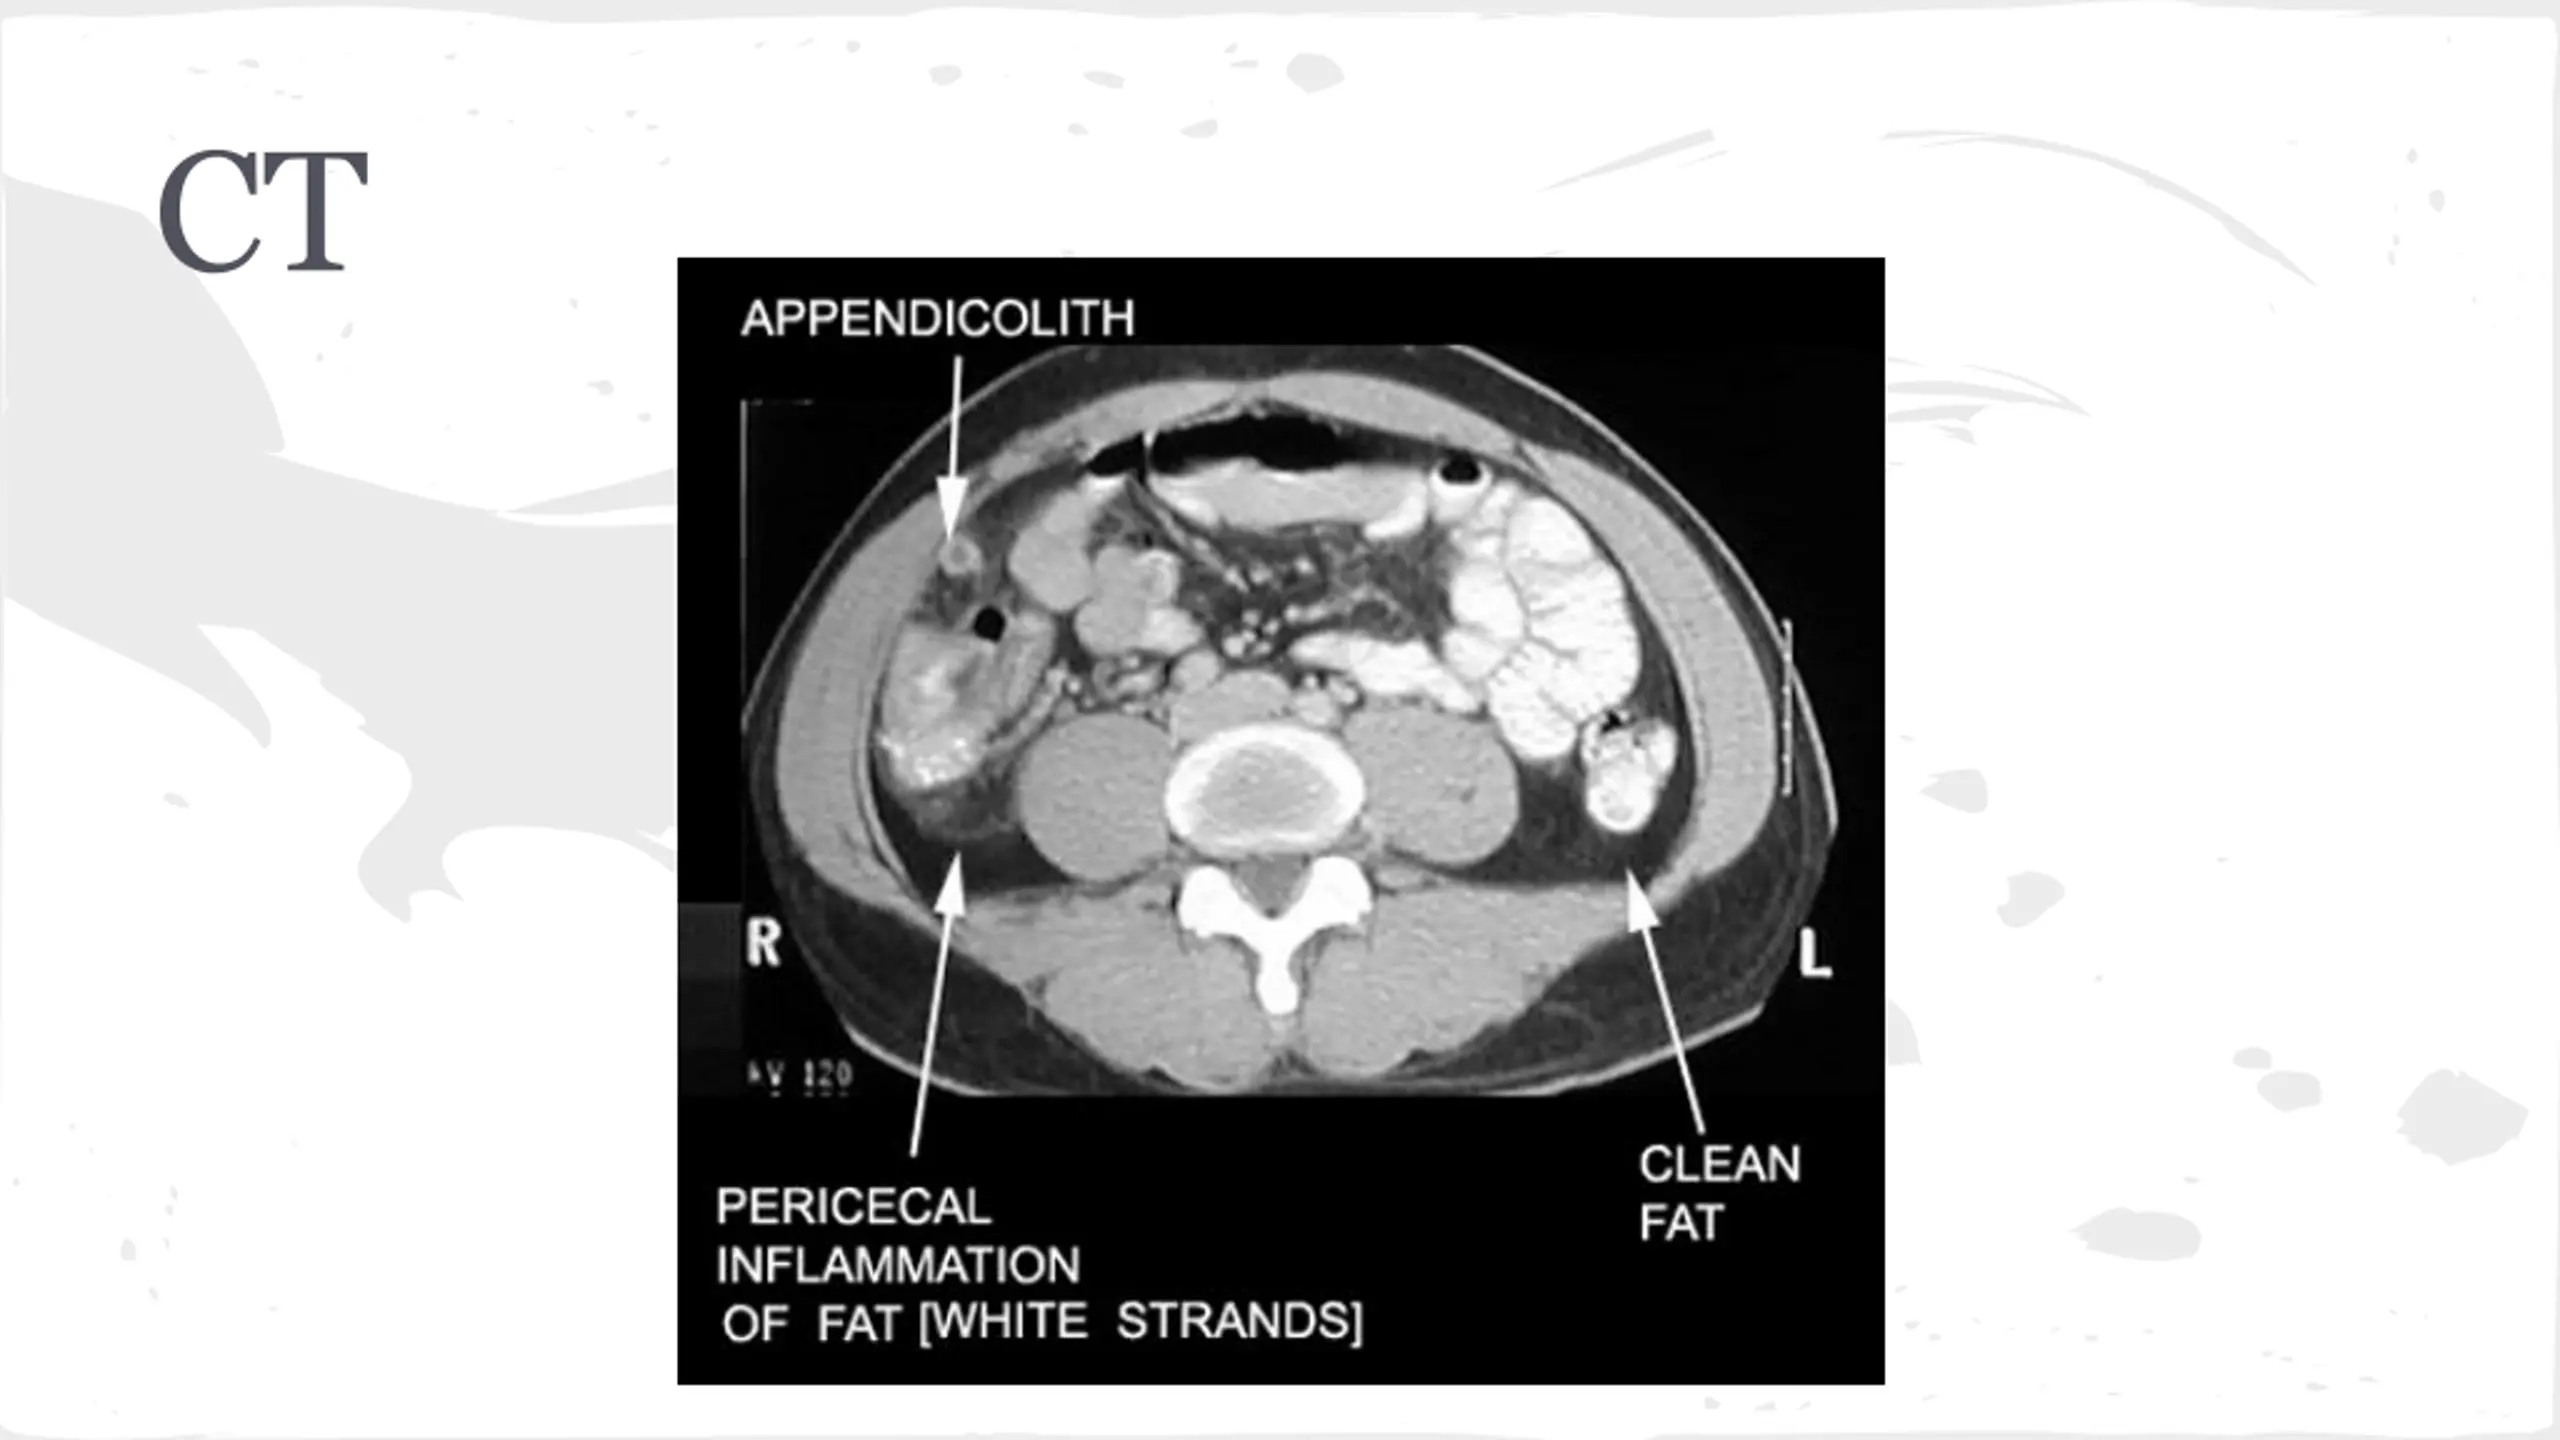

Appendicitis Symptoms Right lower quadrant pain/Periumbilical Pain Loss of appetite Vomiting Exam RLQ tenderness Fever +/- rebound

Appendicitis Test of Choice Management Surgery Consult NPO Fluids Morphine Abx

Findings Gradual Onset, +nausea, +anorexia WBC 12, Hb-14, Lipase-nml, Alk Phos-nml HCG--Negative US: normal Aorta Other Imaging?